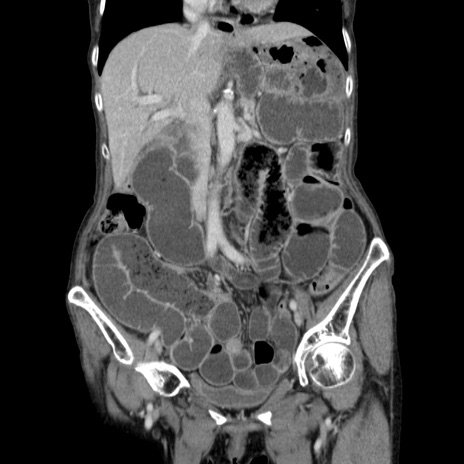

症例25(冠状断像)

【症例】80歳代女性

【主訴】胸のつかえ感

【現病歴】約9時間前に食後から胸のつかえた感じあり、嘔吐あり、来院。

【既往歴】胃癌(全摘)、胆摘、虫垂炎

【身体所見】心窩部に圧痛あり、反跳痛なし。

【データ】WBC 5700、CRP 0.05